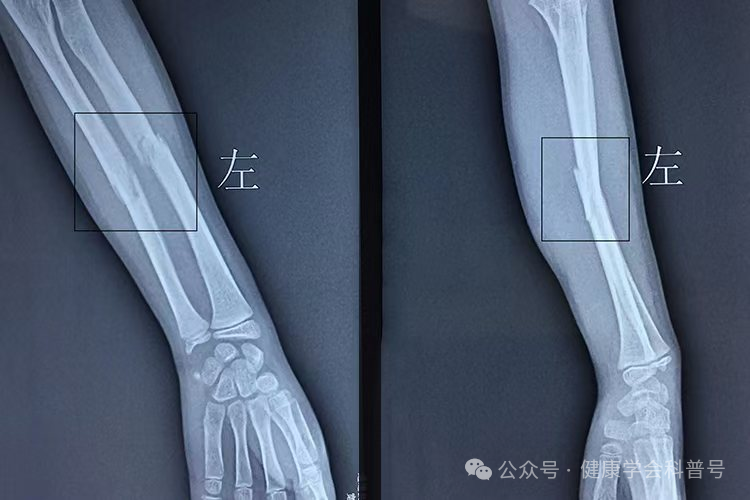

1. 骨折

骨折是指骨骼在受到外力作用时发生断裂或裂痕的现象。骨折的常见原因包括跌倒、车祸、运动损伤等。预防骨折的关键在于避免外力损伤和提高骨骼强度。治疗骨折通常需要手术固定和康复锻炼。在骨折愈合期间,患者应保持充足的休息,并遵循医生的建议进行康复训练。